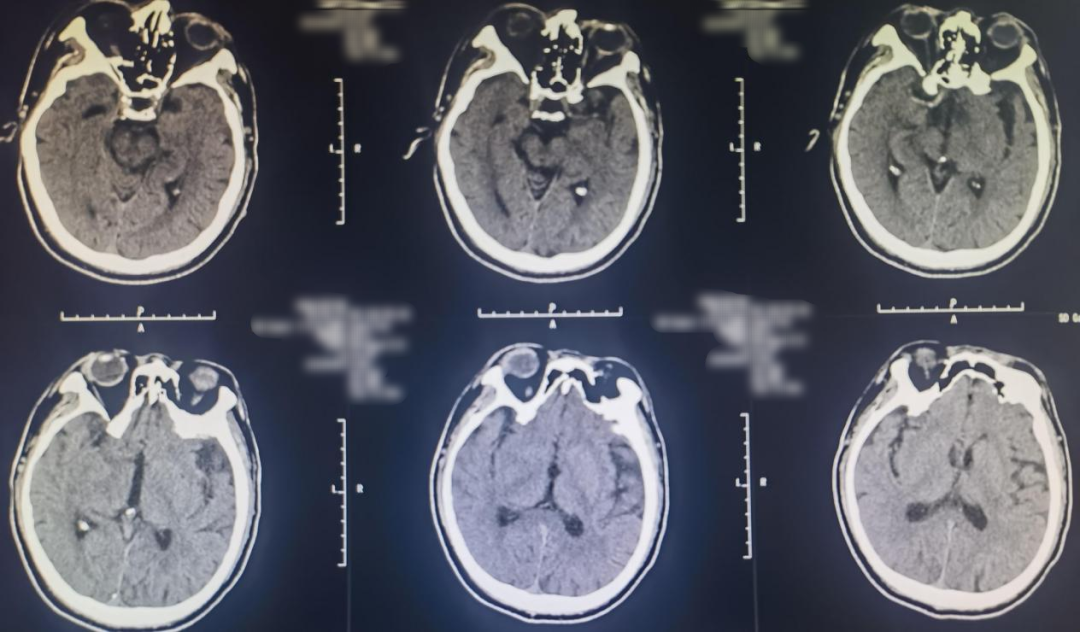

Preoperative Angiography

Cranial CT revealed a hyperdense sign in the right middle cerebral artery.

Preoperative MRI:

Right internal carotid angiography showed occlusion of the right ICA, with no collateral circulation in the right ACA or right MCA, and no compensatory blood flow in the surrounding area.